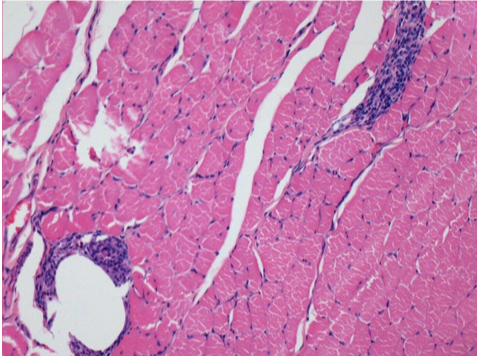

Л: Претибіальний м'яз - без лікування

Через 10 днів після ін'єкції Ендопіл 0,1 мл в правий претибіальний м'яз.

Тут можна побачити утворення вакуолей, які оточені лімфоцитами. Вакуолі відрізняються від некрозу тканини. Присутність лімфоцитів пов'язана з проникністю клітинних мембран.